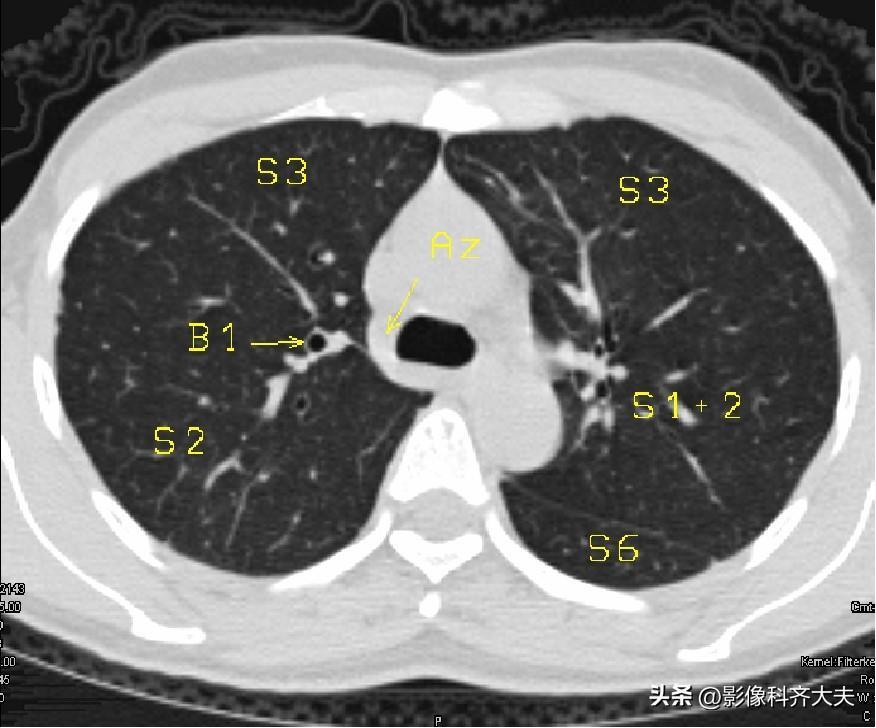

图4-奇静脉弓层面

▲S6:下叶背段